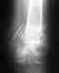

Перелом лодыжки

Скажите пожалуйста, обязательно ли доставать спицы после операции (перелом лодыжки), прошло уже 1,5 года и все неудобства сходят на нет, и какие могут быть последствия. Заранее благодарен

В общем, бессимптомные фиксаторы можно не трогать, но это в общем. Зависит от того, где находятся спицы.